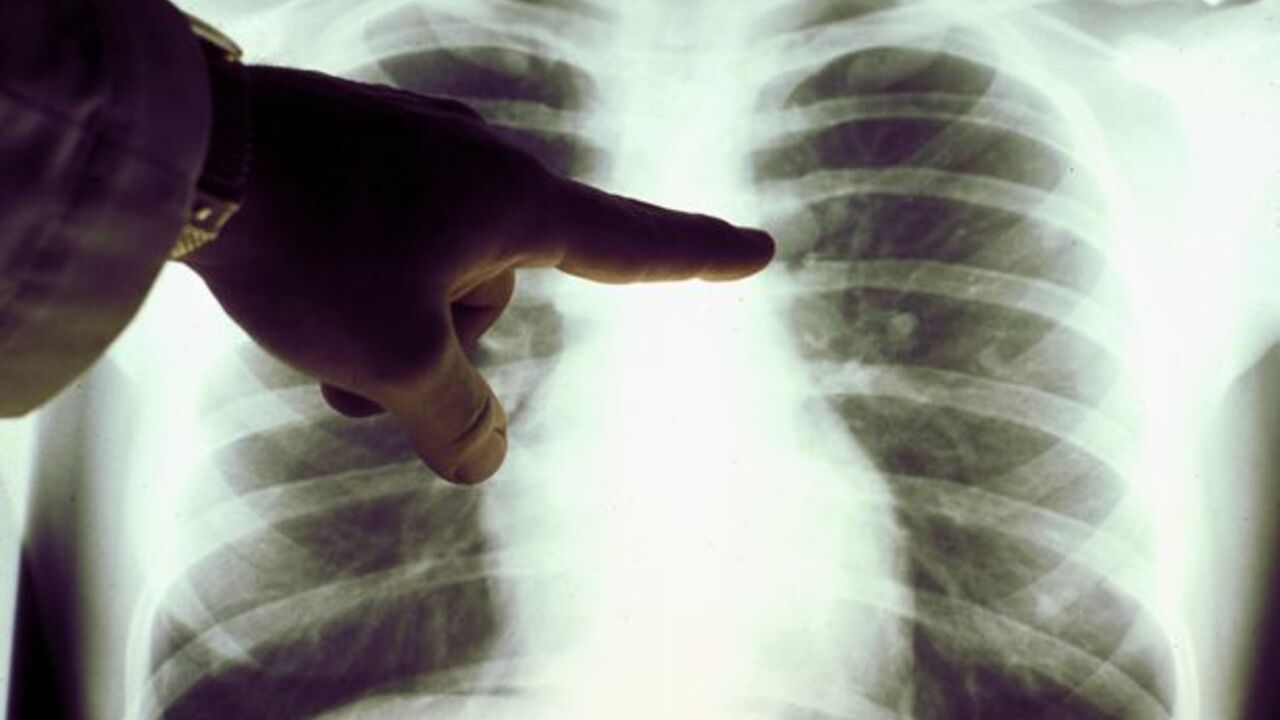

One of the dangerous conditions associated with blood clots is pulmonary embolism. This condition occurs when a blood clot blocks a blood vessel in the lungs and can be life-threatening.

If you notice any of the four symptoms of a pulmonary embolism, call an ambulance immediately. These symptoms include difficulty breathing, pain in the chest or upper back, very high pulse, loss of consciousness.